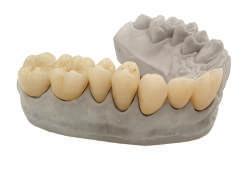

The immediate prostheses are milled in PMMA and fitted on their corresponding bases, adjusted and radiographically checked for proper seating.

After 6 months the patient returns and records are taken for the final prosthesis. In this case the lower prosthesis is made of a titanium bar and a PMMA superstructure and the upper part is made of a titanium substructure and a zirconia structure.